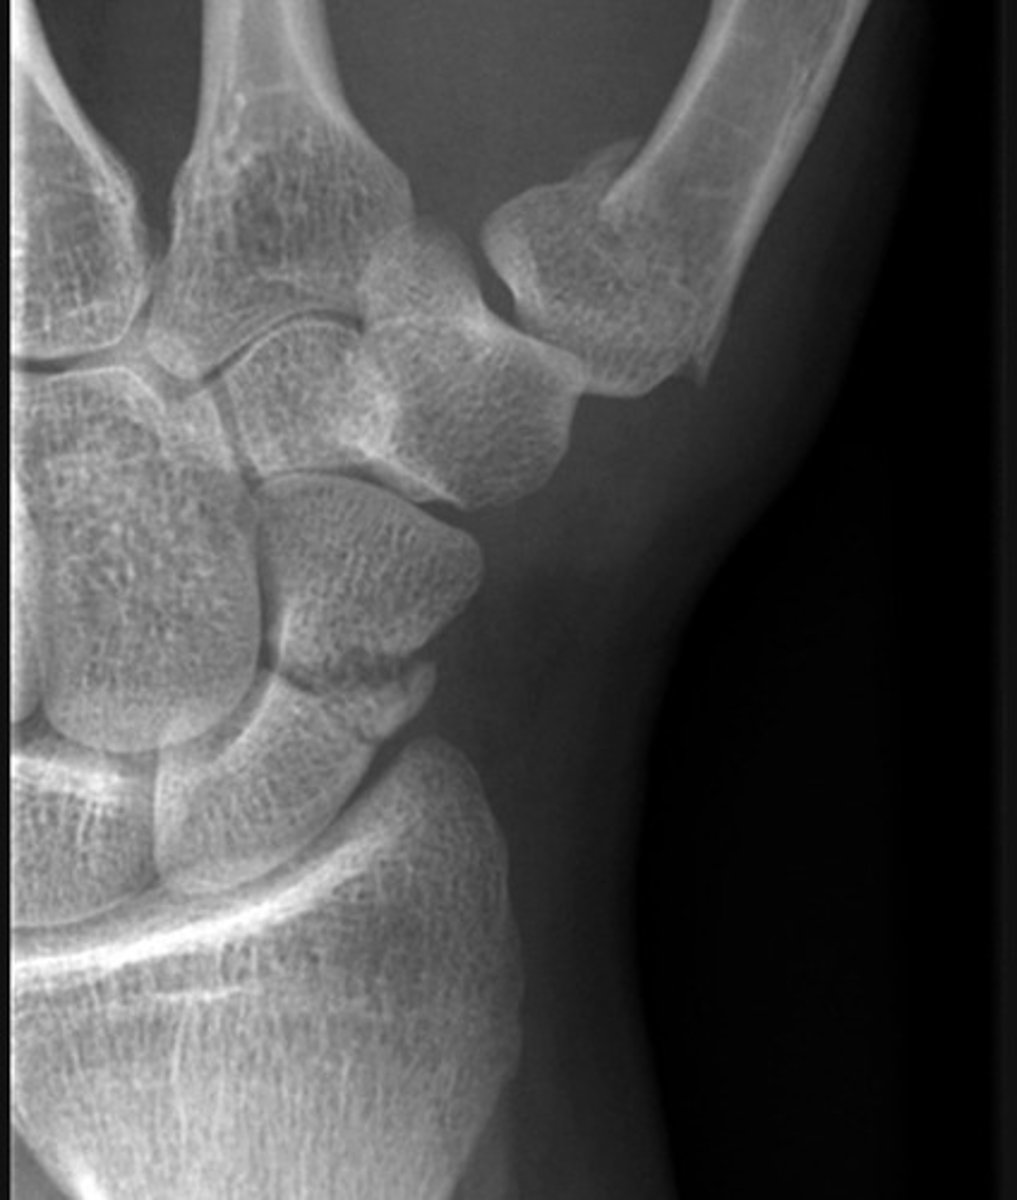

There is a transverse to slightly oblique fracture through the waist of the scaphoid, with no significant displacement or carpal malalignment. Additionally, there is an oblique intra-articular fracture at the base of the first metacarpal, extending into the carpometacarpal joint. The distal metacarpal fragment is displaced proximally and dorsally, consistent with a Bennett's fracture, with associated subluxation at the CMC joint.